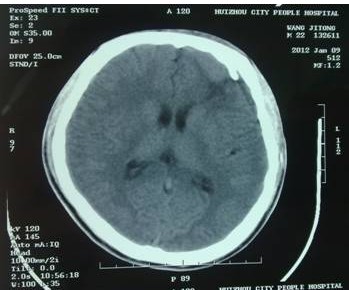

2011年12月,一位患者幾經(jīng)輾轉(zhuǎn)慕名來到我院,求助于余永強(qiáng)主任?;颊邽槟贻p男性,是一名汽修廠工人,由于工作時(shí)輪胎爆炸導(dǎo)致頭部受傷,外院CT提示額骨左側(cè)粉碎性骨折并左額葉腦內(nèi)血腫,血腫量約40ml,已經(jīng)達(dá)到了開顱手術(shù)指征(圖1)。當(dāng)?shù)蒯t(yī)院擬予開顱手術(shù)。但是家屬考慮到開顱手術(shù)的風(fēng)險(xiǎn),同時(shí),由于額骨粉碎性骨折,如果接受傳統(tǒng)開顱血腫清除手術(shù),除了手術(shù)對(duì)腦組織的損傷外,還面臨一個(gè)問題是局部顱骨無法保留,需要再行顱骨修補(bǔ)手術(shù),勢(shì)必增加患者經(jīng)濟(jì)負(fù)擔(dān),也會(huì)在頭部留下不小的手術(shù)疤痕。這對(duì)于一個(gè)二十來歲的年輕人來說也是難以接受的。

圖1:術(shù)前CT掃描,額骨左側(cè)粉碎性骨折,左額葉腦內(nèi)血腫約40ml,手術(shù)指征明確。